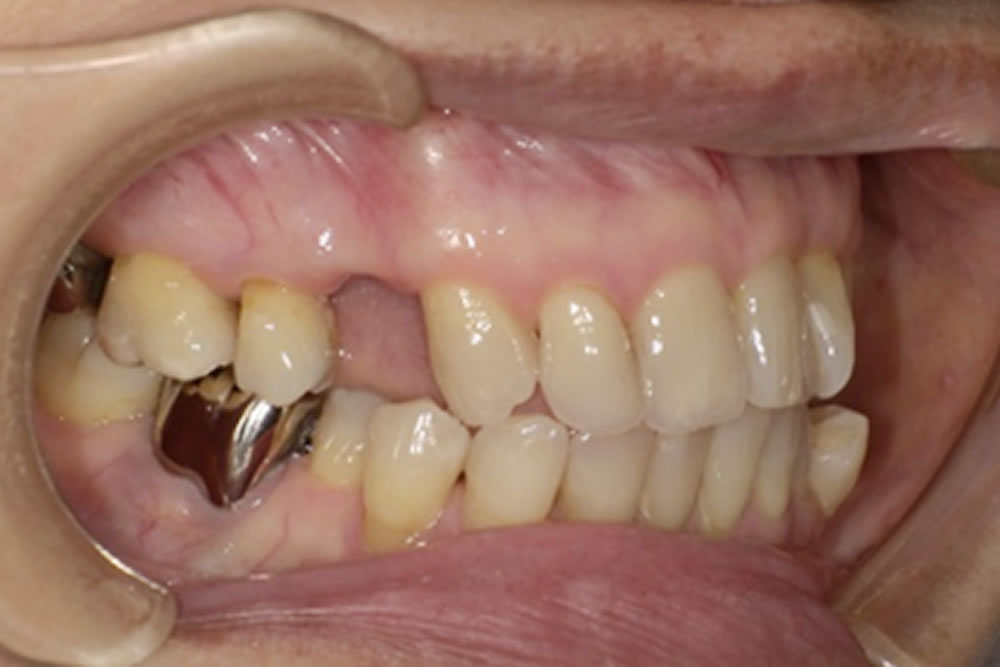

こちらの方は、当院が運営する「入れ歯相談サイト」をご覧になり、無料相談を通じて来院されました。右上の欠損部分をどの治療法で補うべきか検討されており、インプラント・ブリッジ・入れ歯の3種類の治療法について、それぞれの特徴やメリット・デメリットを知りたいというご希望がありました。

次にブリッジ治療も検討されましたが、欠損部の両隣の歯を大きく削って土台にする必要があります。今回の症例では犬歯が支台歯となるため、横方向の力が強く加わり歯根に大きな負担がかかること、また支台となった歯の寿命を縮める可能性があることから、長期的なリスクを十分に説明し、慎重に検討しました。固定式で違和感が少ないという利点はあるものの、清掃が難しく、支台にした歯の状態が悪化すればブリッジ全体の作り直しが必要になる点など、将来的な負担を考えると適応は慎重になる必要がありました。

これらの点を踏まえ、最終的に選ばれたのがミラクルデンチャーでした。外科的処置を伴わず、歯を削ることもなく欠損部を補えること、そして審美性が高いこと、清掃がしやすいことなどが主な理由です。ミラクルデンチャーは特殊な「キーとロック」に似た構造によって高い維持力を発揮するため、最初は取り外しに少しコツが必要ですが、慣れると外れにくく快適に使用できるという特徴があります。